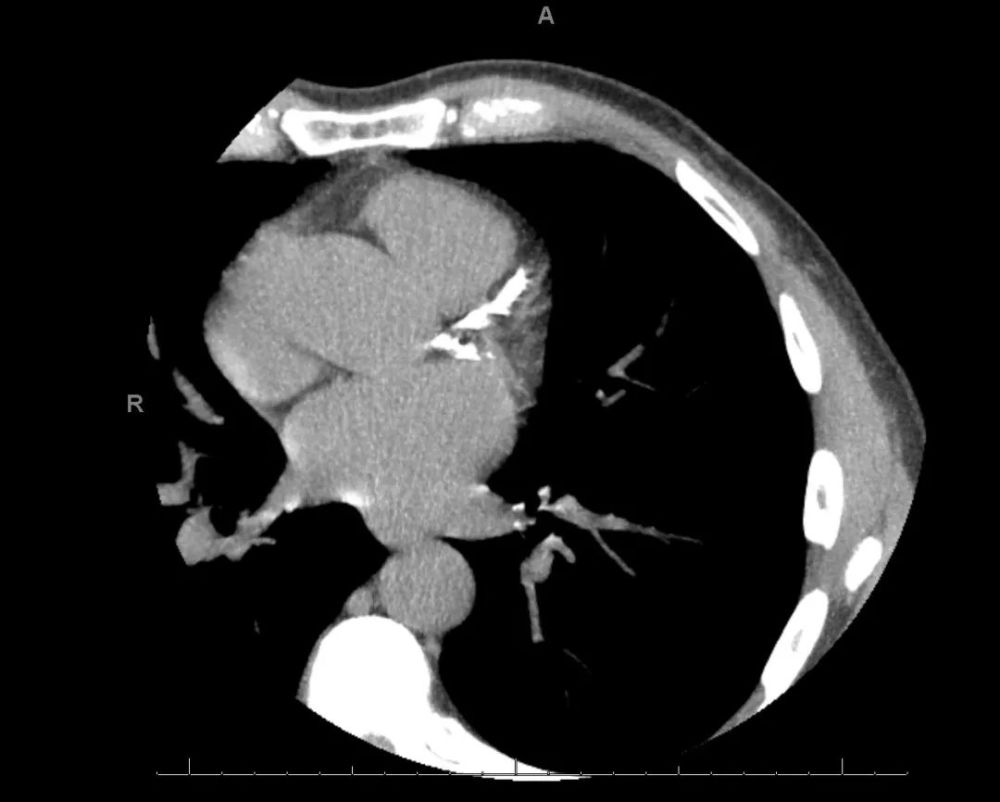

冠脉钙化(CAC)积分是利用CT成像技术来判断冠脉钙化的一项指标 。 在CT图像里 , 钙化会显示为高密度影(白色) , 基于这样的原理 , 对CTA图像里的主要冠脉进行评分 , 得出总的CAC积分 。 通常来说 , 没有斑块或钙化的血管CAC得分为0 , 临床上若CAC积分超过300 , 或经过年龄、性别与种族校正后超过第75百分位则为高危患者 。

本文图片